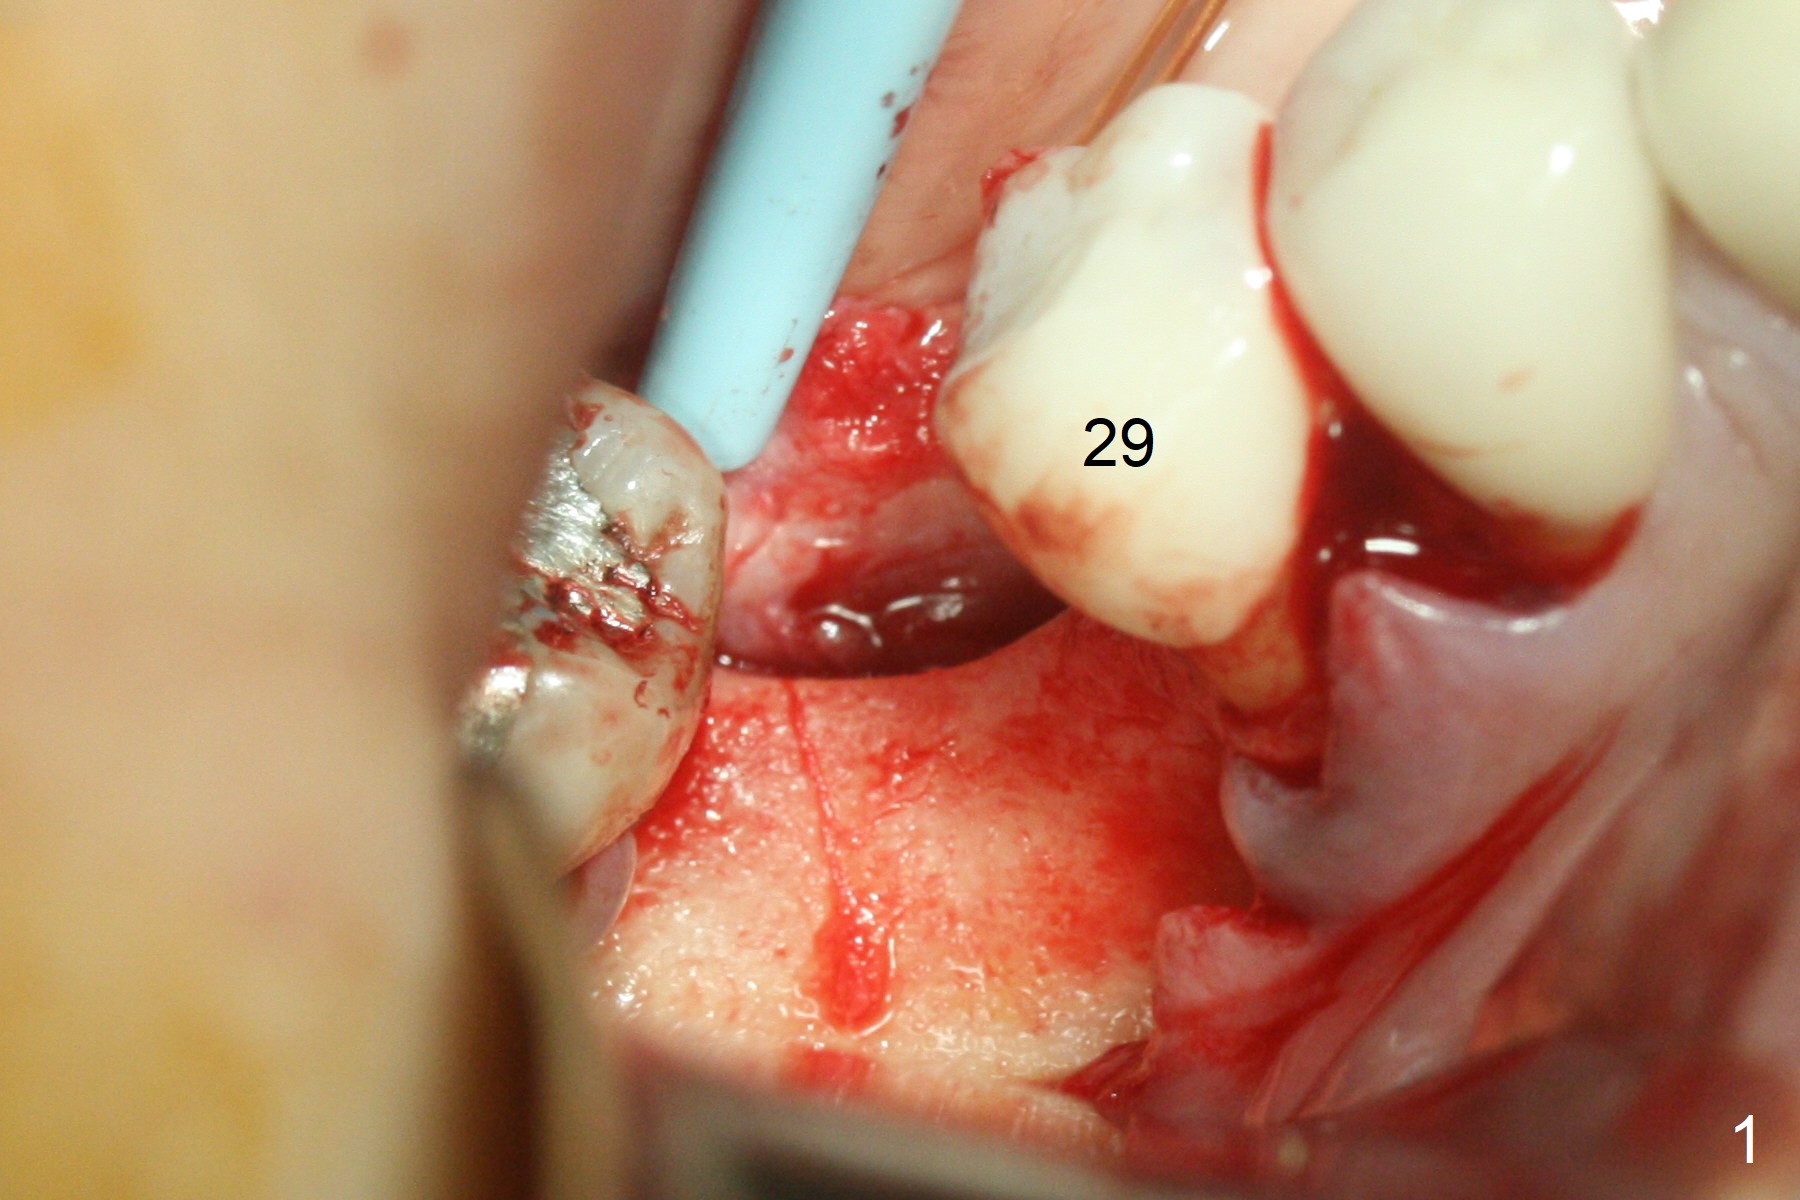

1-Piece Implant at Molar with Narrow Ridge

Incision reveals a narrow ridge and a narrow mesiodistal space at #30 (Fig.1). It seems that a 1-piece implant is indicated. Due to limited mouth opening, a 1.2 mm drill is unstable in place after use for 10 mm; instead a 1.5 mm drill is able to be inserted for 8 mm (Fig.2). A 3x10(2) mm 1-piece dummy implant is placed with 40 Ncm at an apparently acceptable level (Fig.3 >). Clinically a few threads are exposed buccally. When a definitive implant with the same dimension is inserted with 45 Ncm, it looks seated too deep (Fig.4,5). The latter is noted after suturing. The implant is backed up for a few turns so that the length of the abutment appears a little more reasonable. Introspectively, a 4 mm cuff should have been used after ridge reduction. Although there is no bone loss 4 months postop (Fig.6), the abutment margin (Fig.7 arrow) is subgingival (red dashed line: gingival margin). Diode laser is used for gingivectomy prior to impression. The bone density around the implant increases 11 months post cementation (Fig.8 *), probably related to recurrent #18 infection. The patient uses floss after meal.